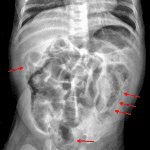

Age: 3

Sex: Male

Indication: Bloody stool

- Pneumatosis involving the descending and sigmoid colon, as well as possibly the ascending colon

- No portal venous gas

- No focal bowel dilation

- Pneumatosis

Pneumatosis involving the descending and sigmoid colon, as well as possibly the ascending colon, which raises concern for necrotizing enterocolitis. No definite portal venous gas. Consider right side up lateral decubitus view to assess for free air.

No bowel obstruction.